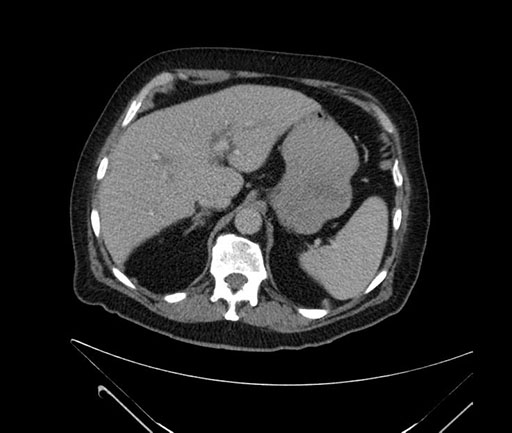

Imaging Analysis

Look through the patient's CT scan to identify any areas of concern for the necessary procedure.

Based on your CT findings, which issue(s) would give reason for "planned slowing down moment(s)" in this case?